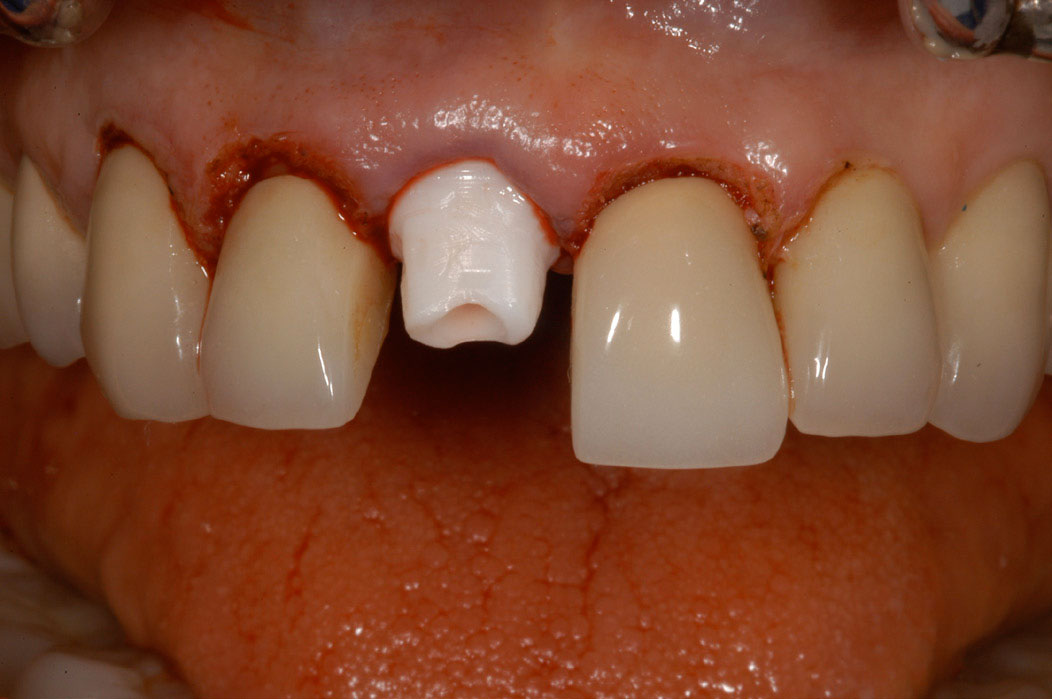

A dental implant most closely replicates natural tooth structure. Once it is osseointegrated, many patients cannot differentiate an implant from a natural tooth. Furthermore, dental implants do not decay or need root canal therapy. Even though the cost is slightly more than a bridge, it is an investment for the future, as implants usually last longer than a bridge. A 10-year report on posterior single implants shows a success rate of 97%.33 Once an implant is placed, the osseointegration and tissue healing time of approximately 4 months is necessary before a final crown is placed. A temporary crown can be placed the same day the implant is placed, but this is only for esthetics, not for function (Figure 15 through Figure 19).

Figure 15 – Extraction of anterior tooth No. 8 without detaching the gingiva.

Figure 15

Figure 16 – Extracted tooth with the root canal material (gutta percha) extending from the apex

Figure 16

Figure 17– A zircon (white) abutment was attached immediately after extraction and implant placement.

Figure 17

Figure 18 – Immediate placement of temporary crown over the abutment; laser crown lengthening was performed on the adjacent teeth to improve gingival symmetry

Figure 18

Figure 19 – Four months after surgery with temporary crown over the implant at No. 8.

Figure 19